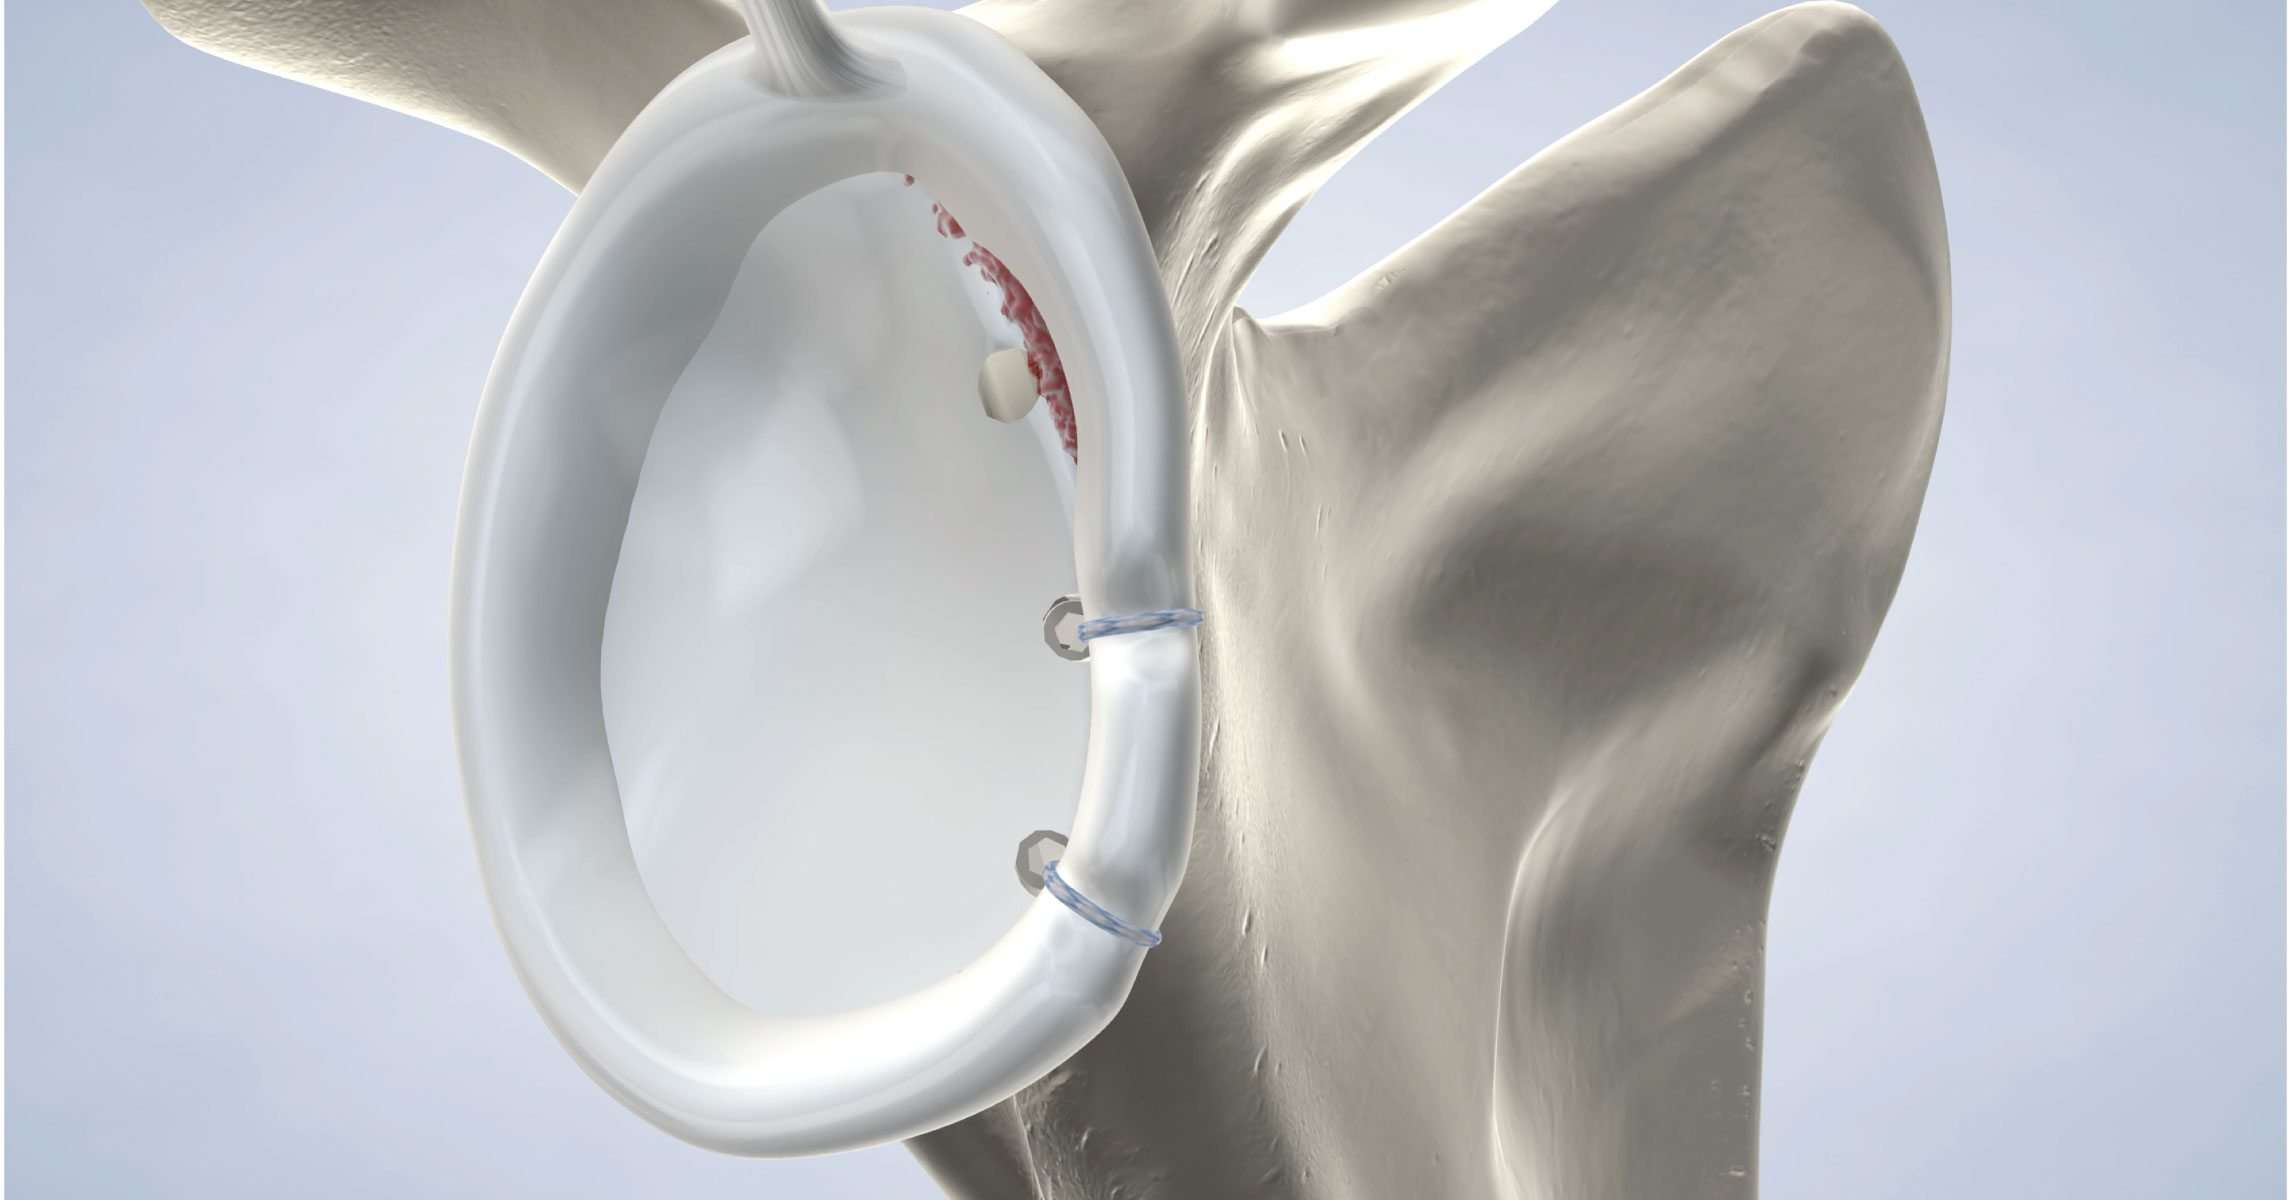

Questo trauma determina nel 90% dei casi il distacco del cercine e dei legamenti (lesione di Bankart) che solo in una bassa percentuale di casi possono cicatrizzare in maniera corretta. La lussazione provoca inoltre con elevata frequenza (80%) una frattura da impatto (depressione) sulla testa omerale definita lesione o frattura di Hill-Sachs se avviene nella parte posteriore o di Mc-Laughin se avviene nella parte anteriore.

Gli specialisti di spallaonline sono in grado nello stesso intervento di reinserire il complesso cercine-legamenti alla glena e di chiudere l’incisura di hill-sachs utilizzando ancorine di fissazione in tessuto di soli 2 mm. -intervento di Bankart plus – In caso in cui il danno ai legamenti o il danno osseo fossero di entità eccessiva si può eseguire un intervento a cielo aperto e in anestesia generale detto di Latarjet.